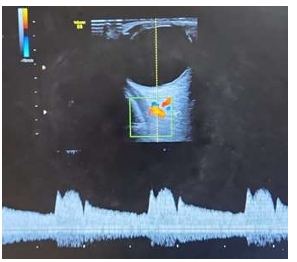

Assinale a alternativa CORRETA que representa a imagem de maior risco para pré-eclâmpsia, considerando as

pacientes com mesmo quadro clínico e obstétrico.